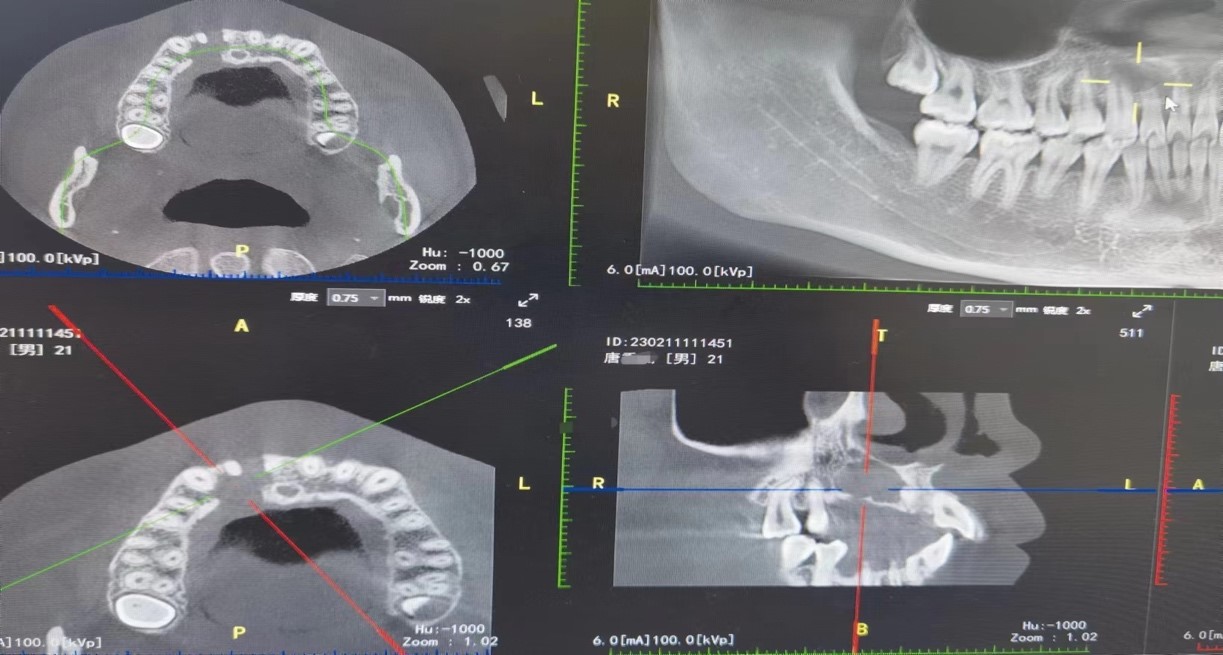

患者小唐,21岁,因“右上前牙舌侧牙龈反复肿胀两年”曾到当地某医院就诊,外院医生根据检查结果,建议小唐拔除患牙后行根尖囊肿切除手术,但其考虑到自己年龄尚小,不想拔牙,恰巧听闻疏勒县人民医院口腔科有来自BV伟德官方网站的援疆专家前来支医,特来就诊。经过梁伟的详细问诊、口内检查及CBCT检查(影像学检查发现:12牙根尖1/3以上根管影像消失,疑似完全钙化,根尖大面积阴影约2x3cm大小,边界清晰)等,诊断为12牙根尖囊肿。